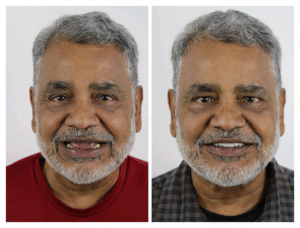

Full mouth rehabilitation, also known as full mouth reconstruction or restoration, is a comprehensive dental treatment that involves restoring the...

A gummy smile or excessive gingival display is a condition where an excessive amount of gingival tissue shows on the...

Introduction-Zygomatic Dental Implants Zygomatic implants are dental implants inserted deep into your upper jaw for the rehabilitation of the atrophic...